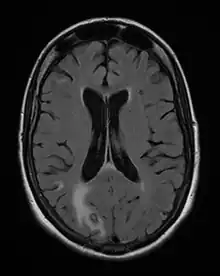

Diagnosis of toxoplasmosis in humans is made by biological, serological, histological, or molecular methods, or by some combination of the above.[62] Toxoplasmosis can be difficult to distinguish from primary central nervous system lymphoma. It mimics several other infectious diseases so clinical signs are non-specific and are not sufficiently characteristic for a definite diagnosis. As a result, the possibility of an alternative diagnosis is supported by a failed trial of antimicrobial therapy (pyrimethamine, sulfadiazine, and folinic acid (USAN: leucovorin)), i.e., if the drugs produce no effect clinically and no improvement on repeat imaging.

- ↑ Nawaz Khan, A (2015). "Imaging in CNS Toxoplasmosis". Medscape Web Site.